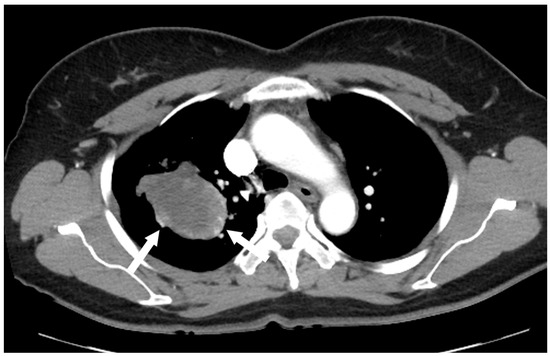

Figure 2.

(a) Unenhanced chest CT showed a homogeneous hypodense mass (5.6 cm in diameter) in the right upper lobe (white arrow). The mass had a well-defined shape with a primarily smooth, but partially beak-like lobulated margin. (b) There was splaying of the anterior and posterior segmental bronchi (black arrow) from the mass effect.